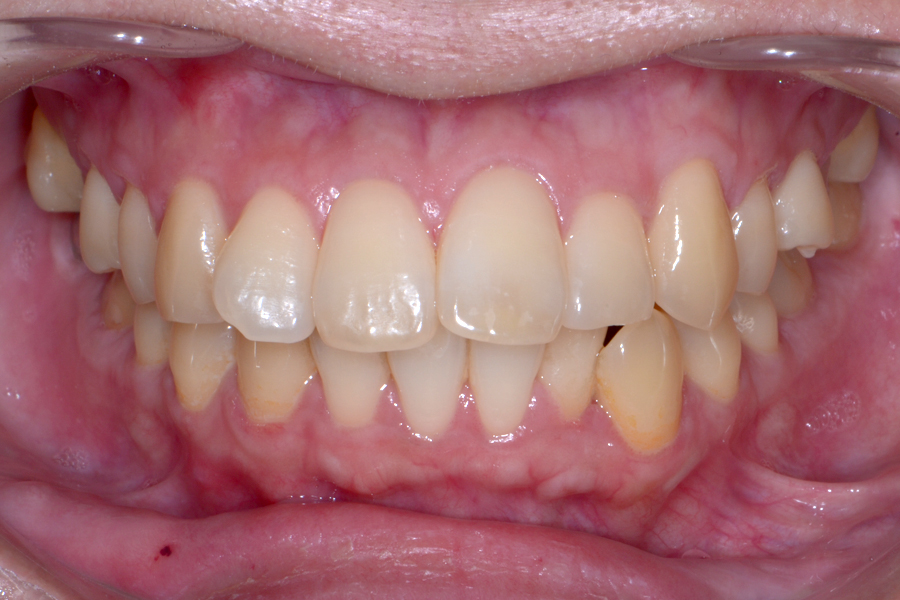

• 治療前

治療後

主訴 結婚式前に前歯を引っ込めたい

治療内容 上顎ラビアル矯正(表側矯正)

リスク 後戻り